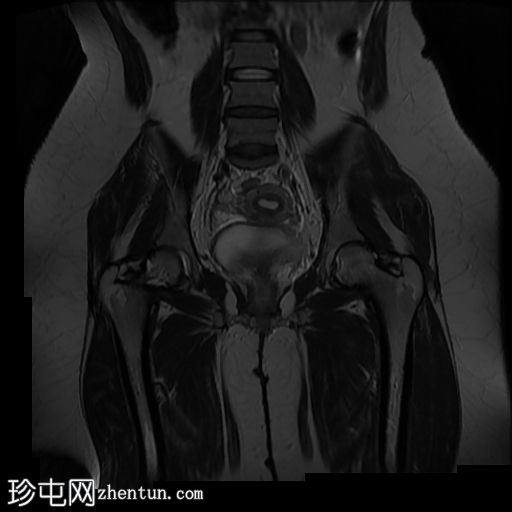

矢状位

T2

偶然发现子宫纵隔,子宫角间夹角为51度,纵隔长度为19mm。

子宫底部可见少量壁内及浆膜下肌瘤。